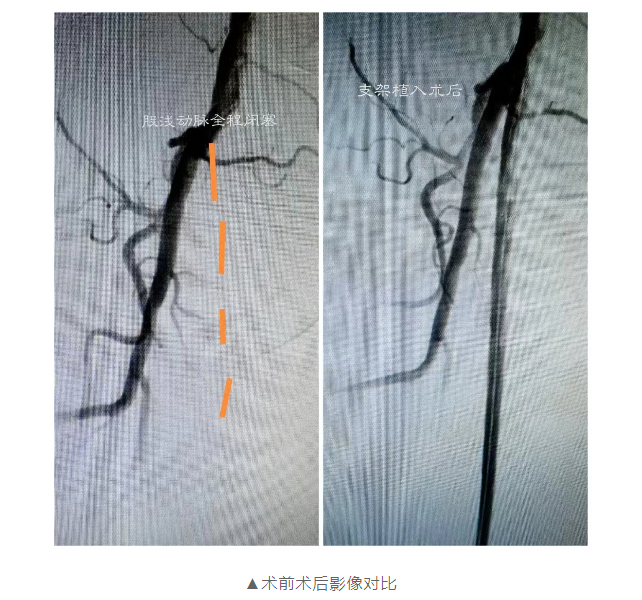

險(xiǎn)些截肢!微創(chuàng)介入治療打通“活血通道”